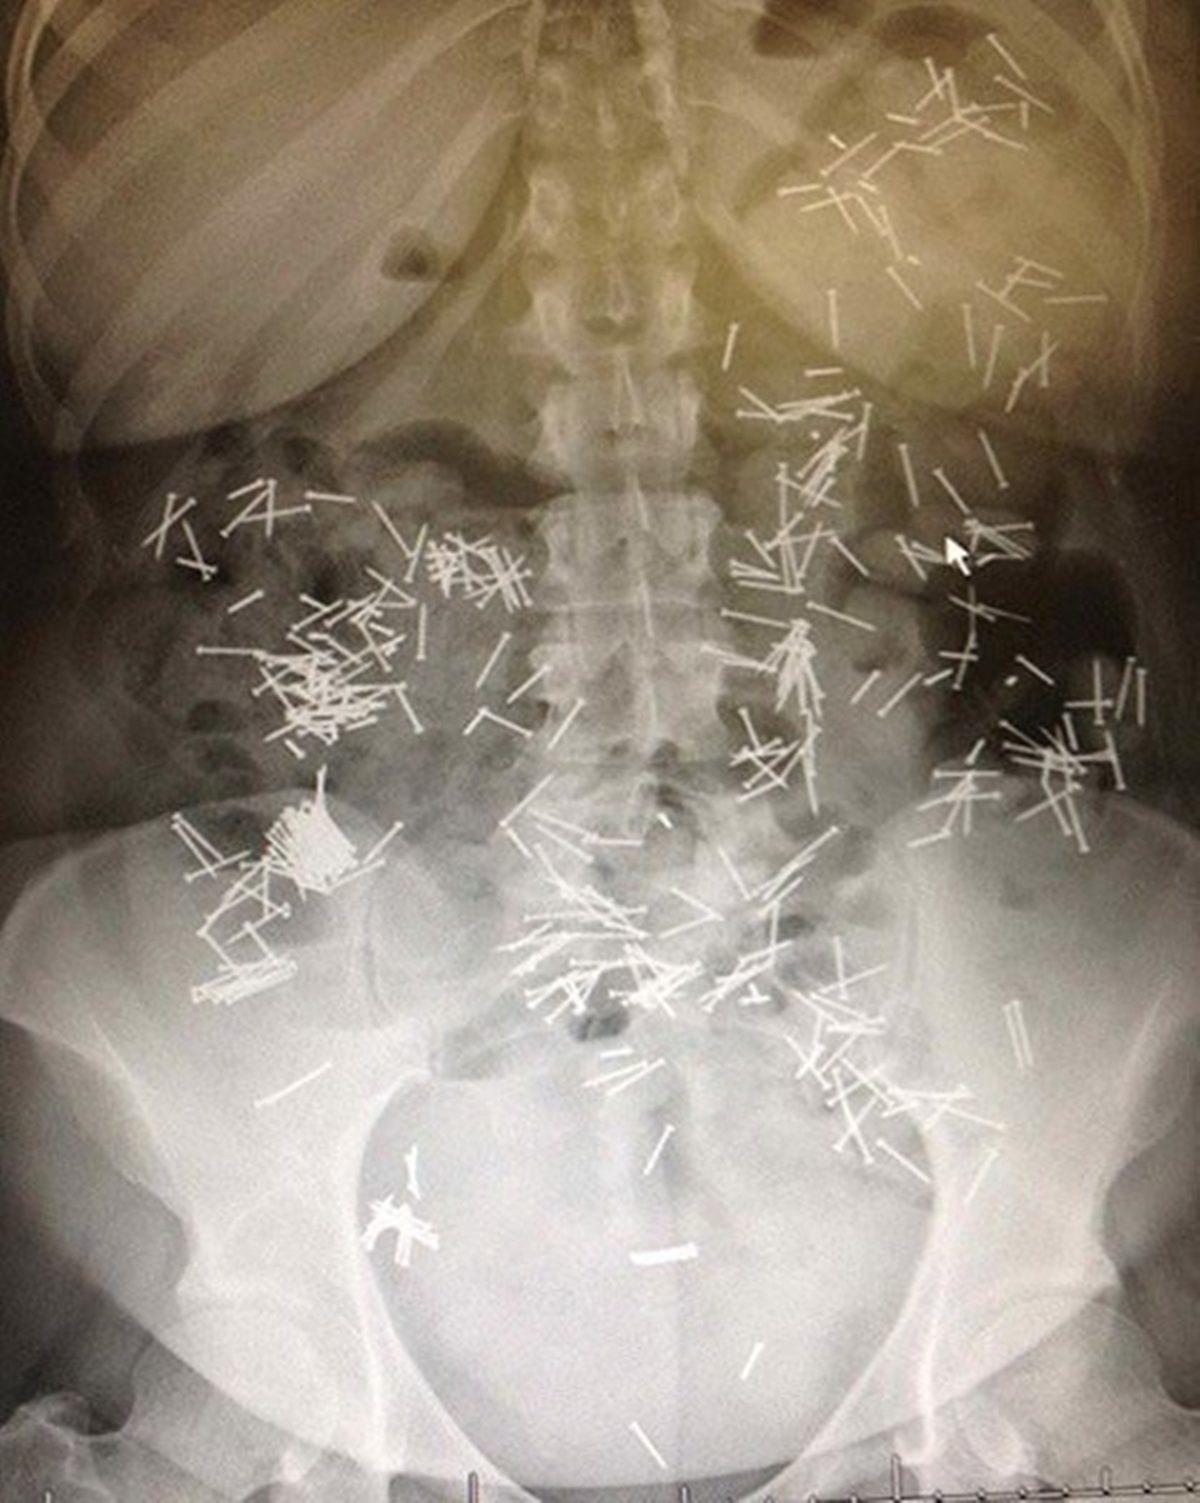

- İç organlarını delmeden geçen küçük çiviler.